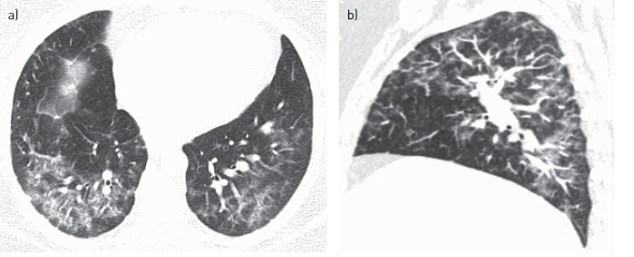

The patient was eventually diagnosed with hard-metal pneumoconiosis after a CT scan.

A CT scan revealed the disease had caused damaged lung tissue to engulf other cells and form ‘giant’ cells that can be seen clearly under a microscope (shown as large white lumps)

The condition creates a distinctive pattern of damage to the lungs that results in breathing difficulties.

It causes damaged lung cells to engulf other tissue and form ‘giant’ cells that can be seen clearly under a microscope.